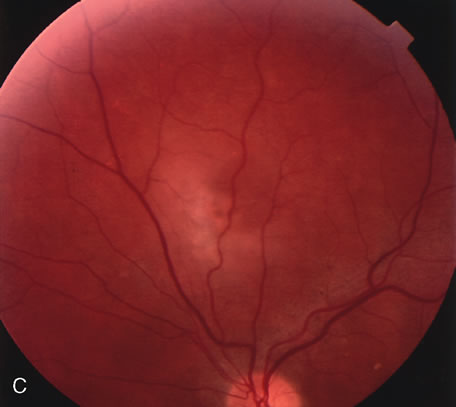

Gentamicin and tobramicin toxicity, which often result from inadvertent injection into the vitreous during cataract surgery, cause devastating retinal damage. In areas where high concentrations of gentamicin reach the retina there is obliteration of the retinal vasculature and ischemic necrosis of the retina (Fig. 43).269,270